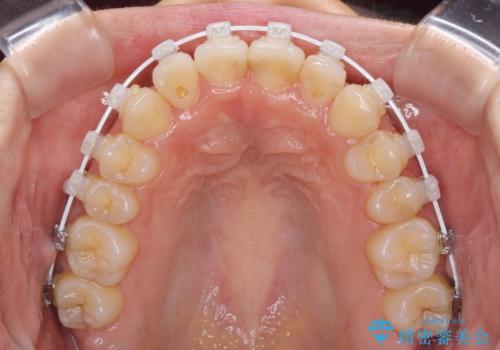

マウスピース矯正では改善に時間がかかる、あるいは改善しきれない可能性があることを伝えたところ、短期間で確実に治療ができるワイヤー矯正を選択されました。

より治療を速やかに行うため、上顎右側にアンカースクリューを使用し、目標としていた1年半ほどで治療を終えることができました。